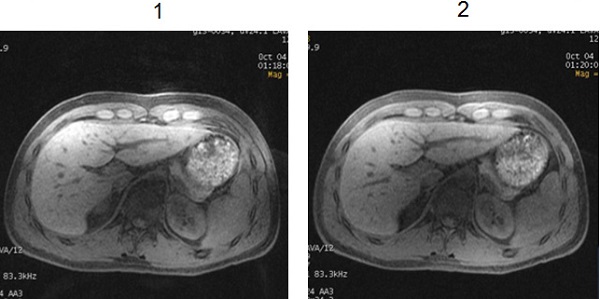

Figure 1. LAVA comparison with Turbo mode on/off

Table 2. Image legend Number Description 1 LAVA image acquired with ARC, scan time 24 seconds. 2 LAVA image acquired with User CV Turbo mode = 1, scan time 15 seconds. - If SPECIAL is selected from the Chem SAT menu located on the Scan parameter screen, a partial Fourier technique in the phase and slice direction is used.